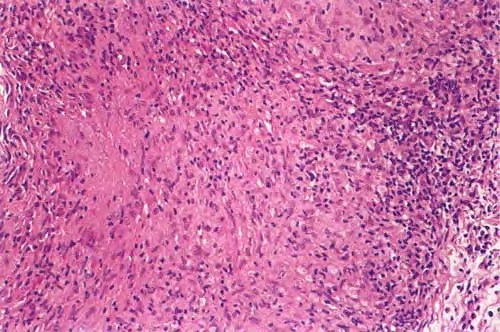

Tungiasis =داء الطوامر Tungiasis Tungiasis is an infestation by the burrowing flea Tunga penetrans or related species. The flea has many common names as listed above. Tungiasis was first reported in crewmen who sailed with Christopher Columbus. The flea is indigenous to the West Indies/Caribbean/Central America region, but it has spread to Africa, India, Pakistan, and South America. Travelers to endemic areas […]